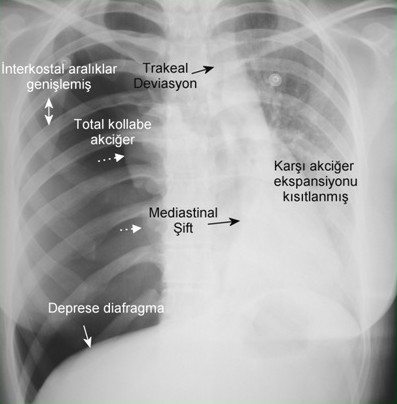

Toraks BT: kesin tanı koydurucu bir yöntemdir. Daha duyarlıdır. Blebleri gösterir, PSP’lilerin %89’unda vardır. Plevral efüzyon pnömotoraksların %10-20’sinde gelişebilir.

Tanı: PA AC grafisinde visseral plevranın görülmesi ile tanı konur. Dev bül – pnömotoraks; klinik ipucudur, pnömotoraks kliniğinde ani dramatik bozulma vardır. Dev bül kronik olduğu için ani gelişen sıkıntılar olmayacaktır. Grafide visseral plevra sınırı belli olmaz, pozisyonla yer değişirmez, sıkışan akciğer hattının açıklığı dışa bakar. Toraks BT kesin tanıda yardımcıdır.

Travmatik pnömotoraks: Künt ve penetran travma sonucu oluşur. Visseral veya mediastinal plevra yırtılması; kot fraktürleri, AC laserasyonları, bronş rüptürü, özefagus perforasyonları. Gizli pnömotoraks oluşabilir. Direkt AC grafisi yardımcı olamaz (subkutan amfizem). BT çok yardımcı. Multitravmalı hastaya mutlaka çektirilmeli. MV bu tür pnömotoraksı hızla arttırır.